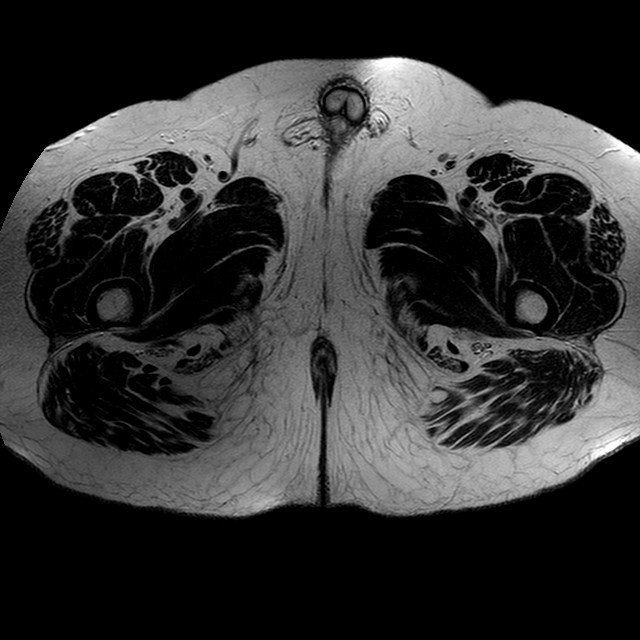

Esami: RMN BACINO

T2w TSE

Evidenti e simmetriche alterazioni osteofitosiche in regione coxo femorale con riduzione delle rime articolari. Degenerazione completa del cercine glenoideo. Non attuali segni di versamento articolare. Non segni di edema osseo che escludono attuale algodistrofia od osteonecrosi. Lieve e simmetrica riduzione del trofismo della muscolatura glutea.